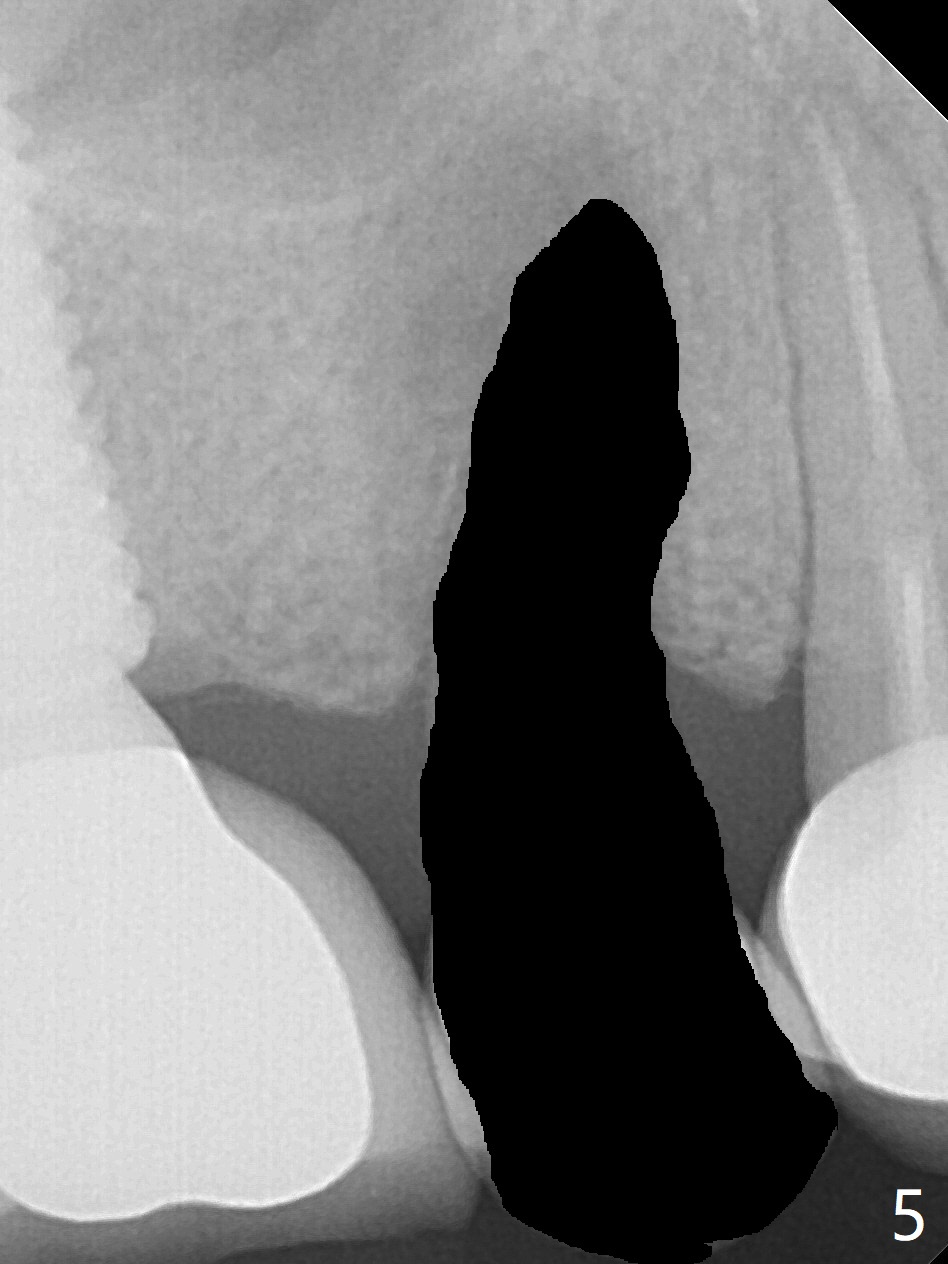

Crown/Implant Ratio

A 53-year-old man has signs of bruxism (Fig.1 diastema *) and root fracture or RCT failure at #4 (Fig.4 (large PARL *)). The RCT failure is related to overload of the affected tooth, which is in turn partially due to infraocclusion of the neighboring implant crown (Fig.1 arrows (implant positioning not ideal)) and partially to due to partial edentulism (Fig.2 missing teeth #14 and 18). For long term, limited ortho will be performed to upright and distalize the tooth #15 (Fig.3 arrow), followed by implants at #14 and 18. For now, the tooth #4 will be extracted (Fig.5), followed by osteotomy in the distal slope of the socket with guide (Fig.6 to get good trajectory). To place a bone-level implant (Fig.7 green), an abutment (blue) with long cuff (pink) is to be used. With poor implant/crown (white) ratio, stress occurs at the junction of the implant/abutment (red arrow), resulting in easy abutment screw loosening. In contrast, stress may be applied to directly to a tissue-level implant (Fig.8 arrow) with less likelihood of abutment screw loosening. The implant/crown ratio improves by approximately 5.5 mm. The roots of the teeth #15 and 16 are so close to each other that interference may occur when the tooth #15 is being uprighted (Fig.9). The empty socket of the tooth #4 is wide buccopalatal (Fig.10); the buccal plate is resorbed coronally (Fig.10 <) so that a 4.5 or 5 mm diameter implant should be placed palatal (Fig.11). Use sticky bone to repair the buccal plate defect and PRF membrane or plug for sinus lift. Following #15 uprighting and distalization, a 5x10 mm implant will be placed at #14; the ridge is triangular (Fig.12 <) so that bone trimmer is needed. A 10 mm long implant will be placed at #18 (Fig.14) to avoid perforating to the submandibular fossa (Fig.13 *).